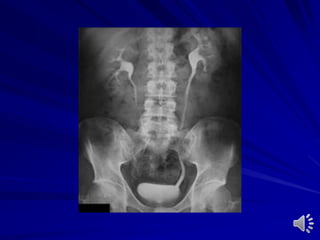

Plain film of abdomen

Disadvantages

Preparation

Radiolucent stones